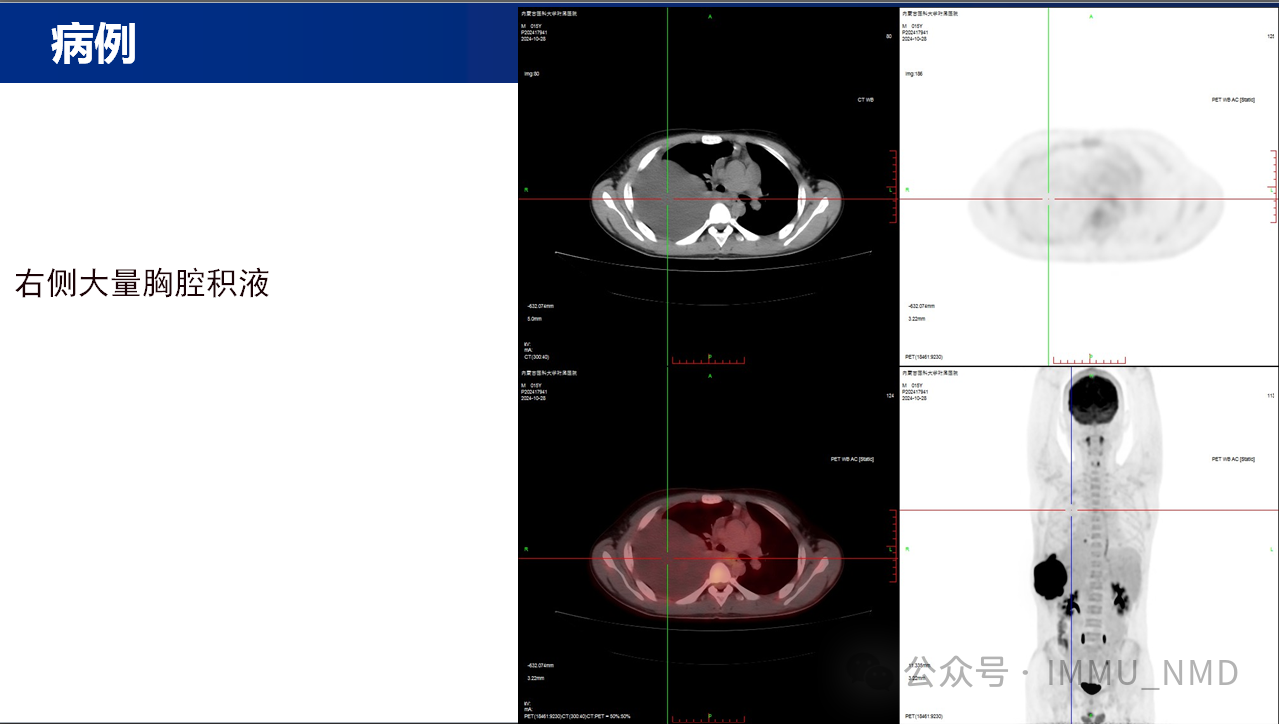

2025年2月27日上午,由核医学科党支部和内蒙古自治区医学会核医学分会青年委员会共同组织的“核先锋”青年医师疑难病例读片会第二十七期暨内蒙古自治区医学会核医学分会青委会青年医师疑难病例读片会第七期于线上腾讯会议及线下核医学科示教室成功举办。参加线下读片会的有党支部的全体党员医生及非党员医生、研究生、规培生、进修生,参加线上读片会的有青委会多名医生,读片会由张国建教授做最后总结。